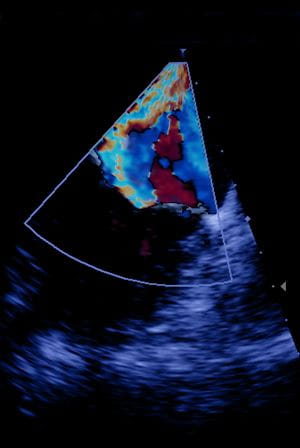

In the operating room and with Leah asleep, the team worked together, threading a tiny, fabric-covered metal clip through a puncture in the femoral vein in Leah's leg and up to her heart using a tube called a catheter. Using ultrasound and X-ray to guide them, they positioned the clip directly at the area where the mitral valve was leaking and then released it, pinning the two leaflets together and reducing her heart's regurgitation.